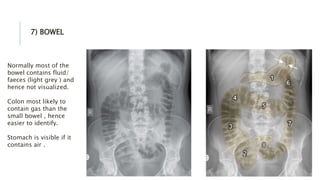

7) BOWEL

Normally most of the

bowel contains fluid/

faeces (light grey ) and

hence not visualized.

Colon most likely to

contain gas than the

small bowel , hence

easier to identify.

Stomach is visible if it

contains air .